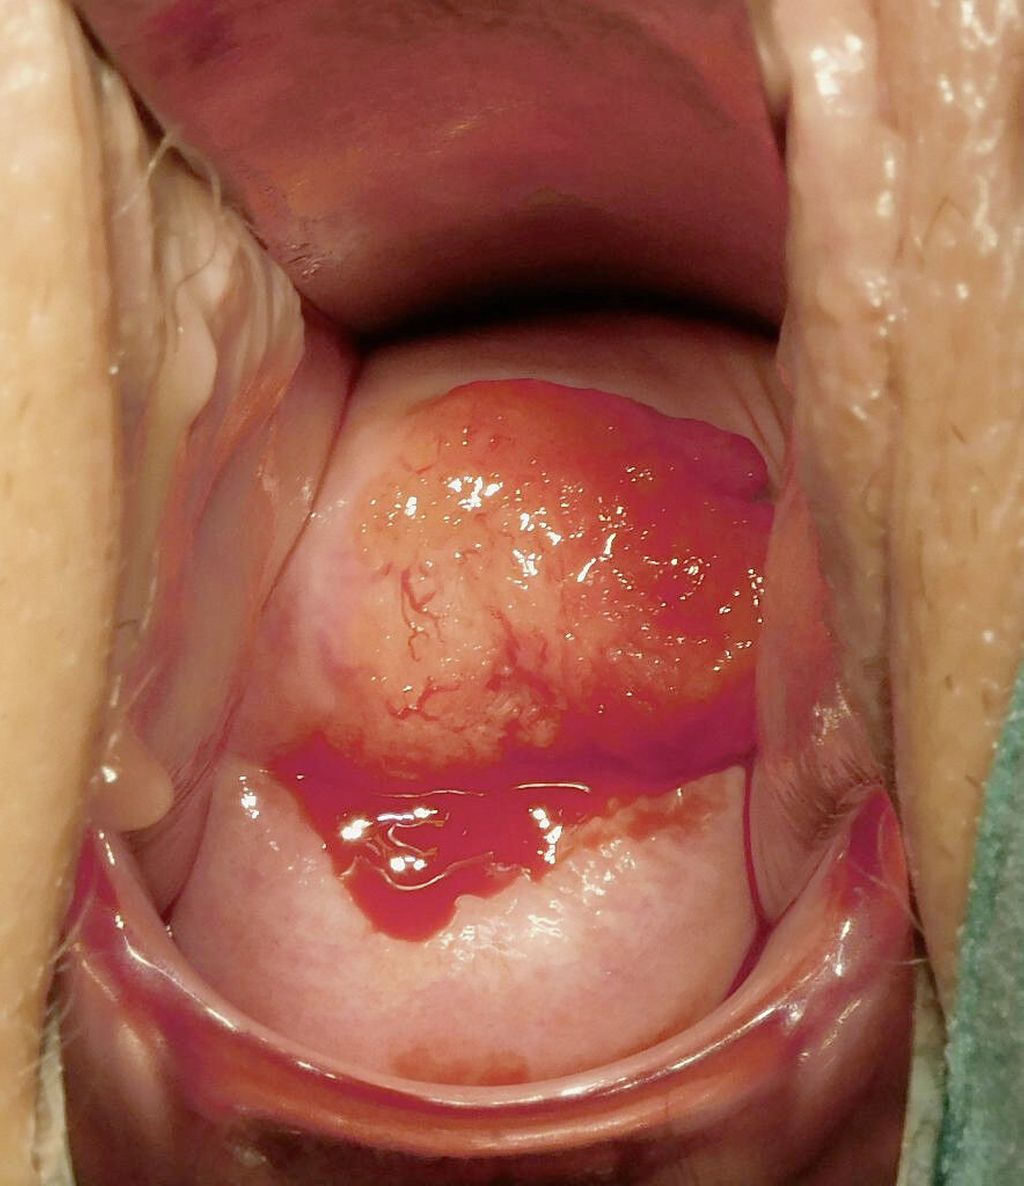

Heute werden in entwickelten Ländern die meisten Zervixkarzinome in einem früheren Stadium diagnostiziert, die pathologische Evaluierung der Läsionen und Operationspräparate ist detailliert, und moderne Technologien stehen uns für Diagnostik und Therapie zur Verfügung. Frühe Zervixkarzinome werden meist operativ, lokal fortgeschrittene Tumoren mit primärer Radiochemotherapie behandelt. Freilich bleibt das Zervixkarzinom in Entwicklungsländern eine führende krebsbedingte Todesursache.1

Operative Therapie

Sehr kleine Zervixkarzinome (FIGO Stadium IA, Mikrokarzinome) können meist mit Konisation alleine fertilitätserhaltend oder mit einfacher Hysterektomie behandelt werden.